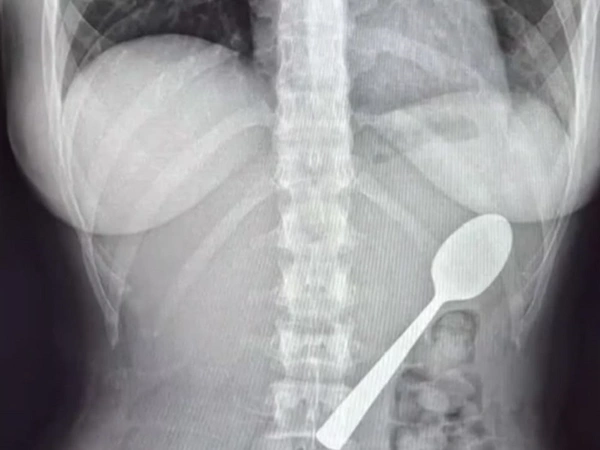

Στη συνέχεια η γυναίκα κατέβαλε μάταιες προσπάθειες να απομακρύνει το κουτάλι από την άνω πεπτική οδό της. Προκειμένου να μην πνιγεί, αναγκάστηκε να καταπιεί το αντικείμενο των 17 εκατοστών.

Ήταν μόνο αφού τελείωσαν με το γεύμα τους που η 28χρονη δέησε να πάει στο νοσοκομείο, όπου οι γιατροί το αφαίρεσαν με γαστροσκόπηση, και την ίδια να συνεχίζει κανονικά της ζωή της.